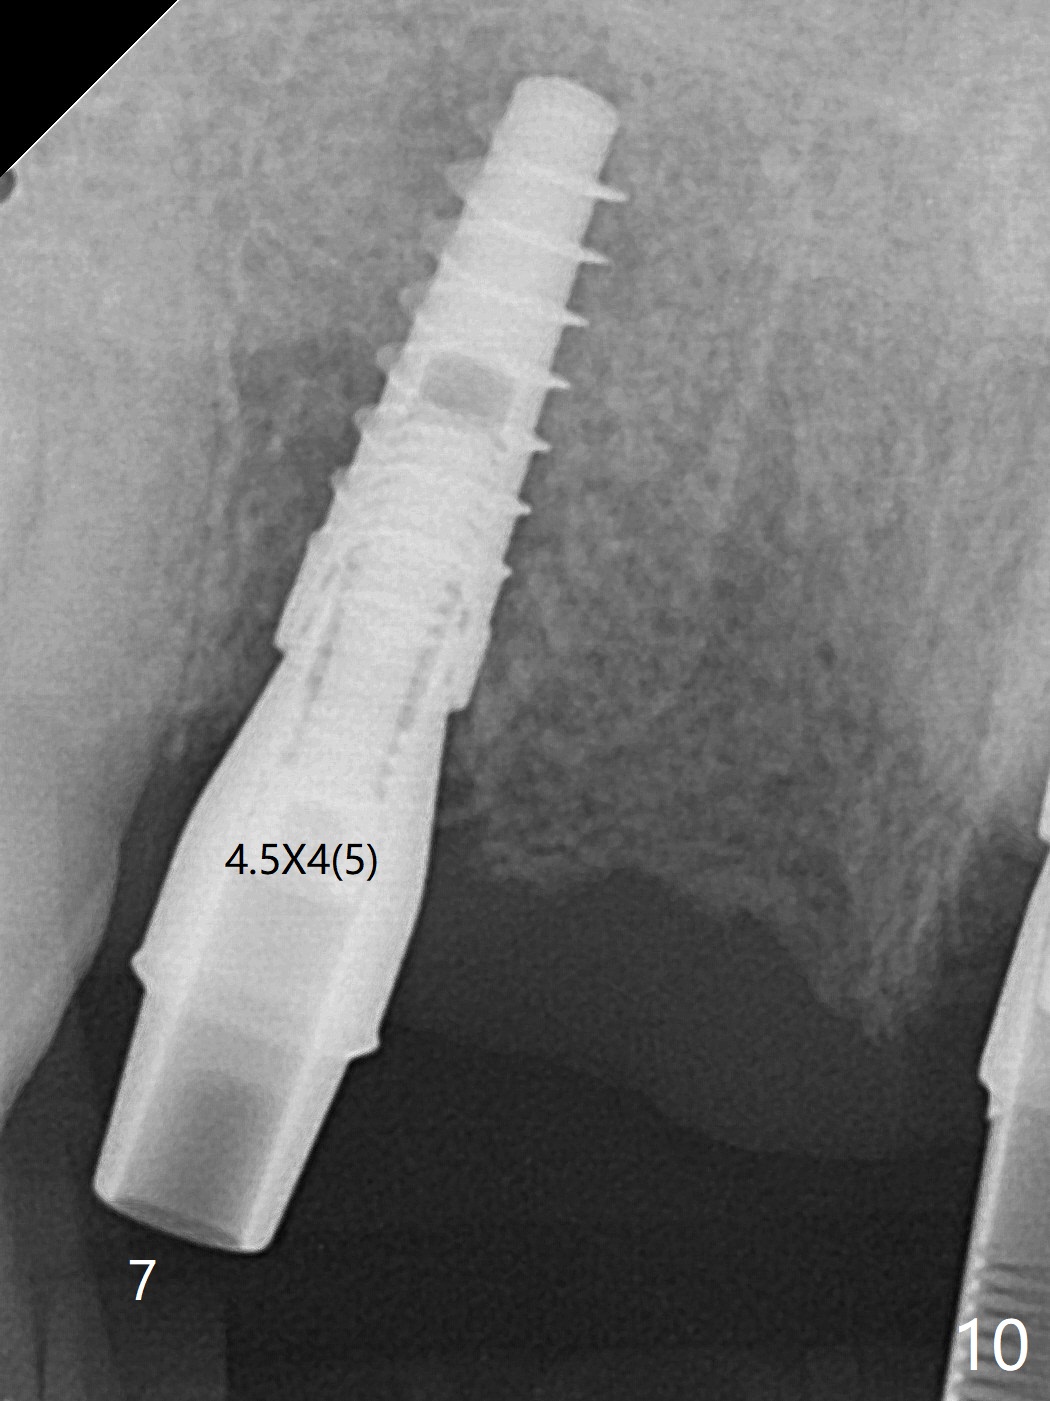

今天下午进入治疗室,粘性骨粉已制备:上清液来自红管(含促凝剂),离心3分钟(图一);再离心10分钟上清液就转变PRF,压制后,使用前剪成三块(图二:黑线),其中两块punch一个洞(图二:圆圈),插入7,9号牙基台固定;大块覆盖11/12号牙牙槽窝(图十四)。7,9,11,12号牙必须拔除(图三),然后在7,9,12种植。由于缺失左下磨牙,前牙垂直距离减少(图四)。完成9号牙位钻洞后,利用fixture mount(图五:M)植入植体,并留在原位固定导板(图六),然后7号牙种植,也留下fixture mount(图六:7,9),最后完成12号牙植入,但是后者扭力低,放置愈合螺帽(图九),而7,9号牙位放置修复基台(图七,八(使用5.5毫米profile drill后),好像基台没有完全就位。7号牙位更换基台似乎没帮助(图十),9号牙位再次放置同一个基台临床上仿佛有改变(比较图八与十二)。放置粘性骨粉后(图十一至十三),牙槽窝口覆盖PRF膜(图十四:P(A:基台)),最后使用树脂敷料固定骨粉和膜(图十五,六),基台帮助敷料固位,没有咬合干扰(图十七:*)。树脂敷料部分解决美观问题,一个月后撤除,如果植体仍有稳定性,可能制作7-10临时牙桥,可能部分维持或者恢复牙龈外形。术后一周病人主诉后面植牙和鼻底疼痛,11号牙根尖牙龈充血(图十八),轻度触痛,可能与术中尚未完全清创有关(图十九(术前CT 3D图像))。再服用Amoxicillin一周,症状好转,鼻底轻度触痛(图二十)。术后1.5月没有任何不适,撤除树脂敷料,7号牙基台(袖)显得太长,换一个短的(4.5x4(5)(图十,十一)->4x4(3)毫米)毫米),植骨好像愈合正常(图二十一:*)。7号牙换了短的基台,9号牙基台高度调整后,与对合牙有足够空间做临时牙桥,最好8,10号牙位牙龈应该凹陷(图二十二:*),有pontic外形。另外9号牙基台颊侧牙龈边缘有所修整,临时牙桥准备。先做7-10临时牙桥,理想临时牙桥pontic处树脂应该多些(图二十三:白线)压迫牙龈形成凹陷。11,12号牙牙槽窝在树脂(Bosworth)敷料下也正常愈合(图二十四)。